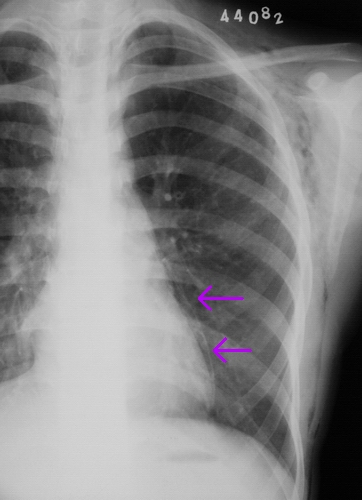

左侧胸壁、腋窝、颈部及右侧颈部皮下软组织内示斑片状、条状低密度气体影,四天后复查片明显吸收好转。

左侧气胸、皮下气肿、结合病史可考虑哮支炎。

皮下气肿。纵隔气肿.考虑支气管哮喘。